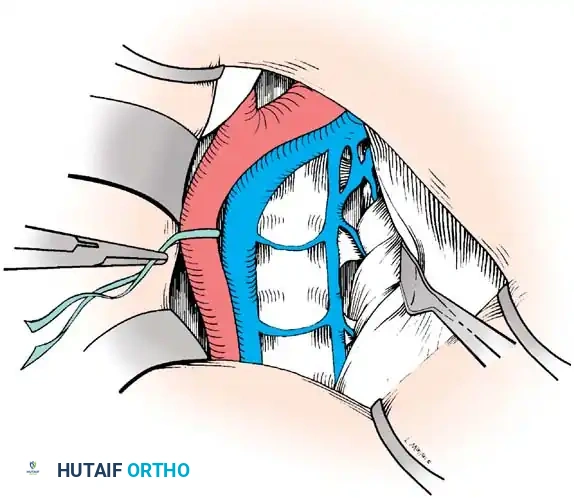

Vascular Management at the Bifurcation:

The approach to the L5-S1 disc space is dictated by the anatomic level of the aortic bifurcation.

* High Bifurcation: The safest approach is directly between the common iliac vessels. The primary vessels encountered here are the middle sacral artery and vein, which must be cauterized and divided.

* Low Bifurcation: The approach must be made lateral to the aorta, vena cava, and common iliac vessels. To safely mobilize the left common iliac vein to the right, you must meticulously isolate, ligate, and divide the iliolumbar and ascending lumbar veins. If a higher exposure is needed, ligate the 4th and 5th lumbar vessels.